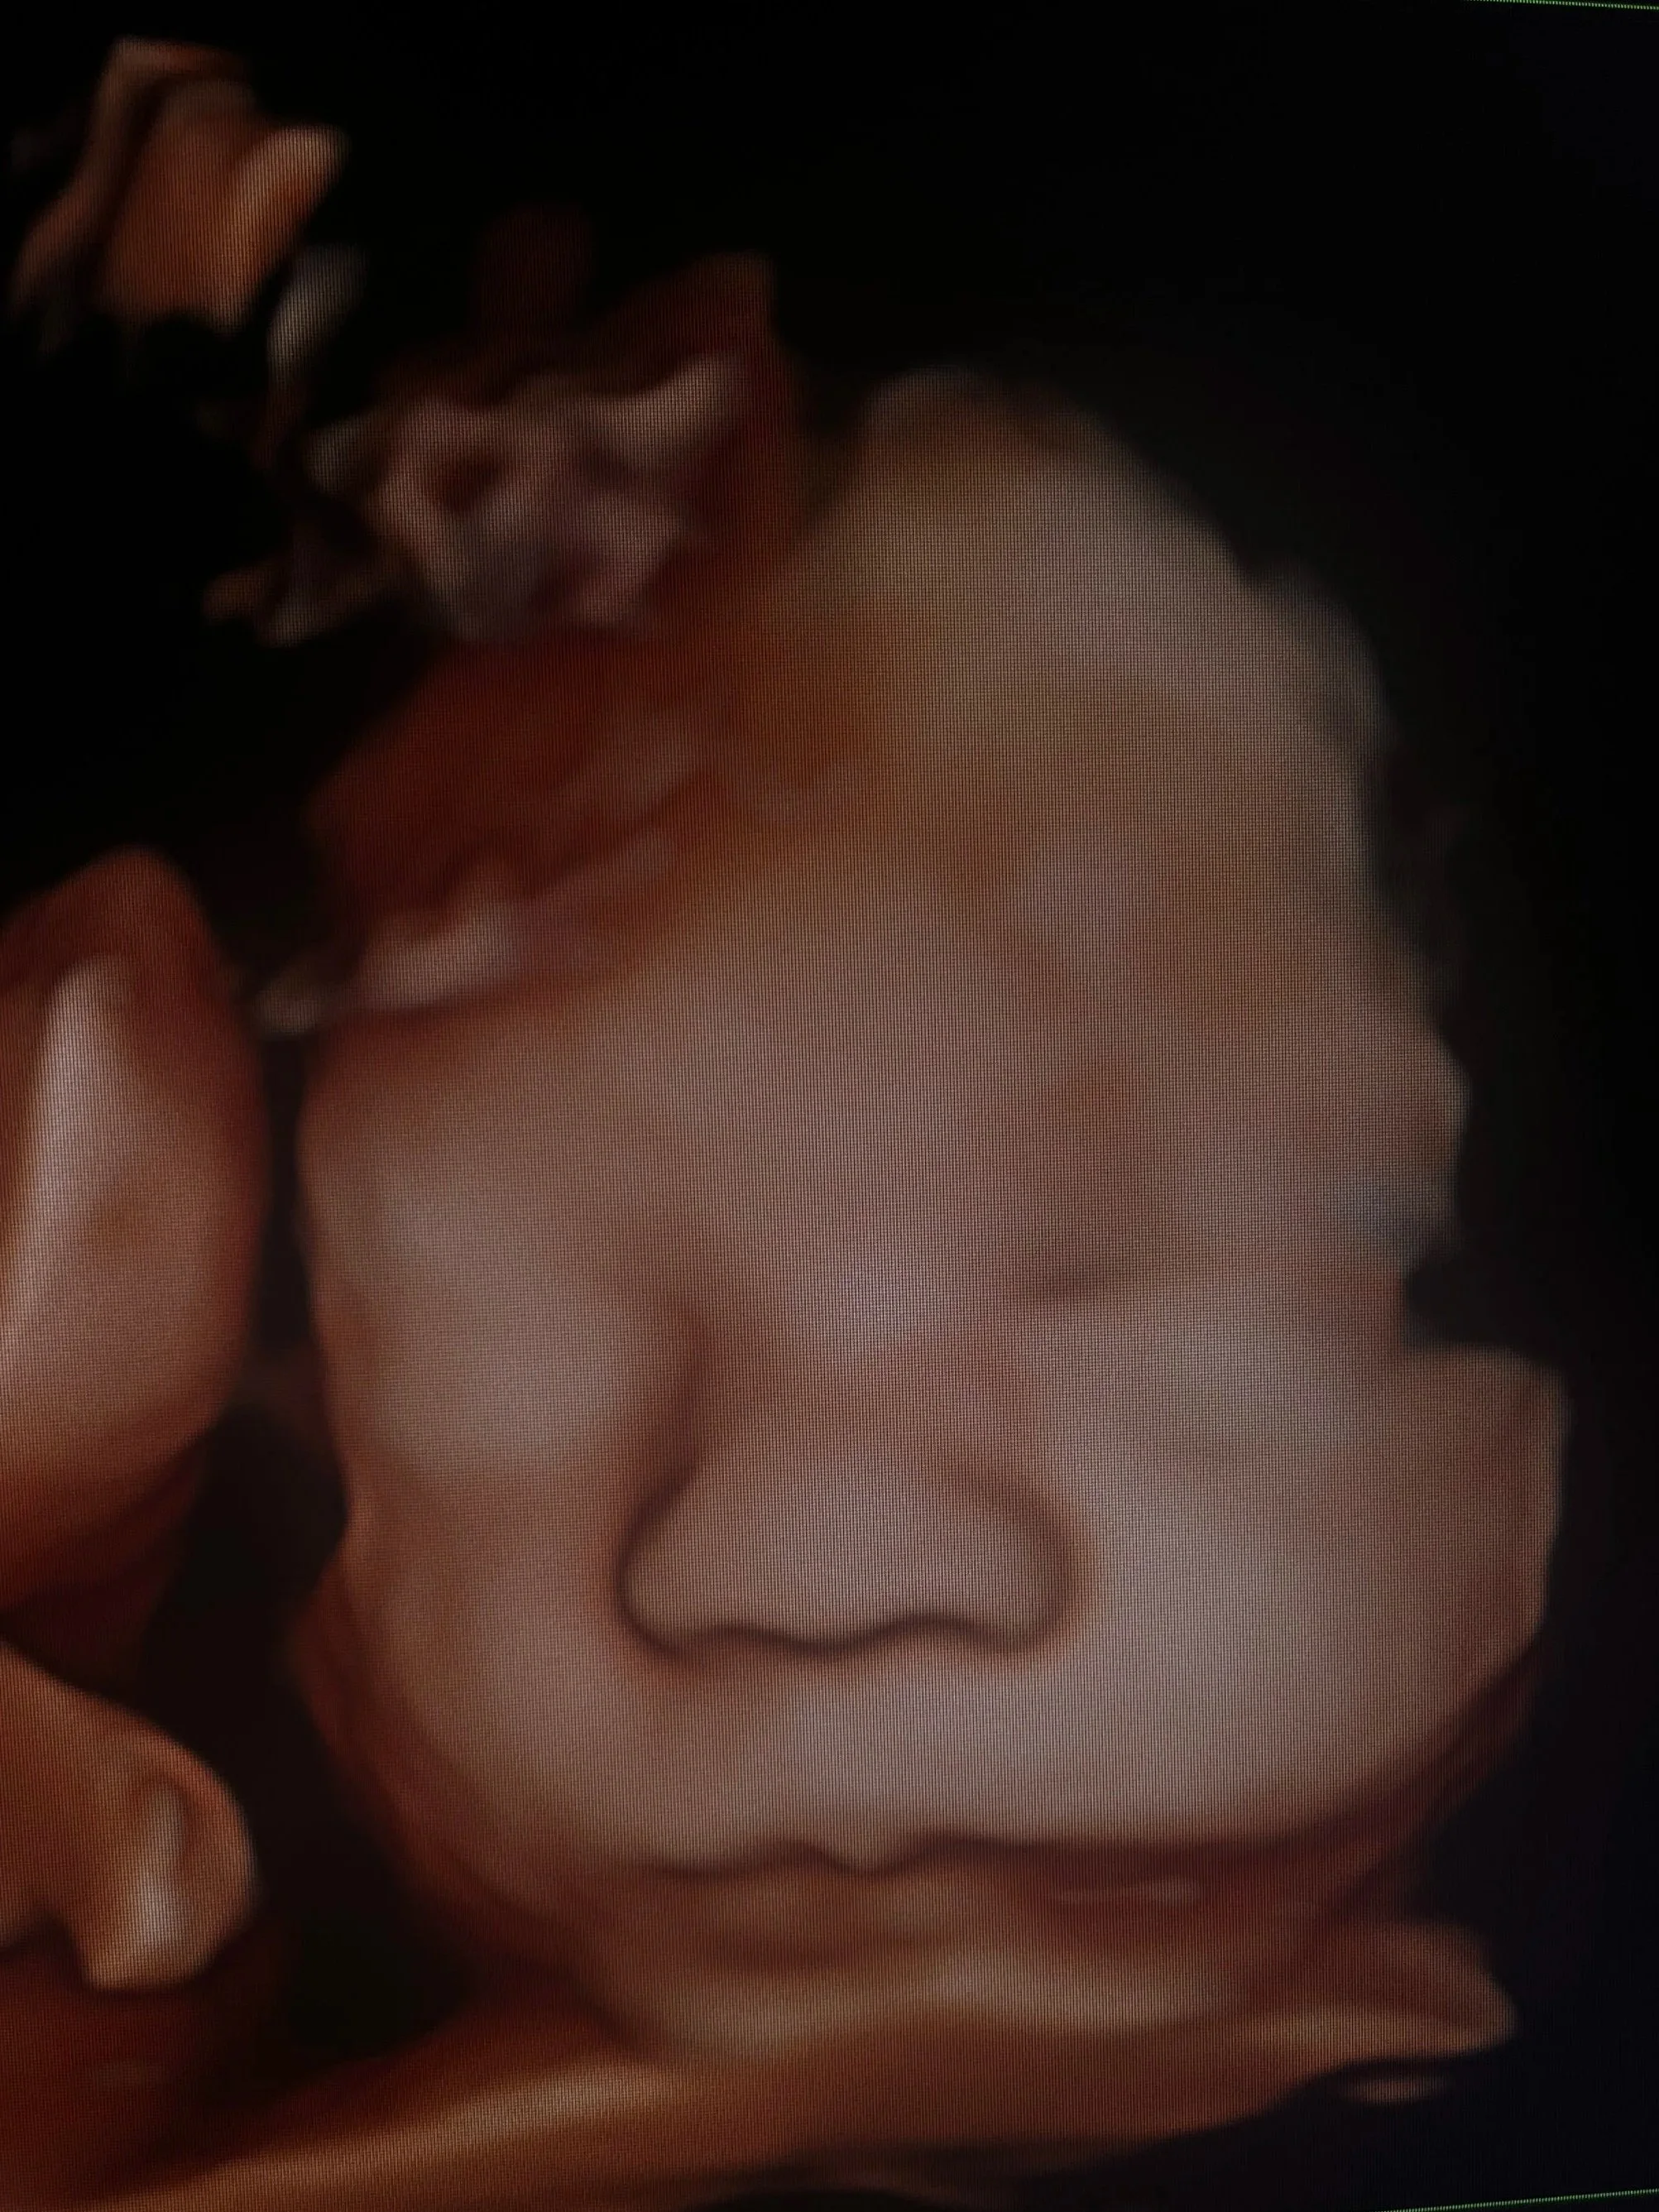

The Baby Gallery